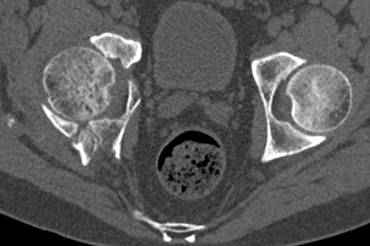

Интересно было бы посмотреть рентгенограммы до операции. У меня впечатление, что я не все вижу, что тут есть... Уважаемые Господа "тазисты" и "тазологи", к какому типу переломов вертлужной впадины по Летурнелю вы бы отнесли это случай?

Из переломов проходящих через крыло и/или заднюю стенку ни простой перелом "передней колонны" (явно имеется пером задней стенки, и не видно перелома седалищной или лонной), ни простой "поперечный", ни ассоциированный "Т-образный" (т.к есть перелом крыла и не видно перелома седалишной), ни ассоциированный "задняя колонна+задняя стенка", на ассоциированный "поперечный+задняя стенка", ни ассоциированный "передняя колонна+задняя гемисфера" (не видно перелома седалищной), ни ассоциированный "обе колонны" (не видно перелома лонной седалищной) не подходят под эту классификацию....

к таковым себя не причисляю, но...обычное дело для нашей страны - выкладывать 3D и не показывать стандартные проекции Judet. Дигност представляет те ракурсы, которые по-его мнению наиболее информативны, более того комп сам достраивает какие-то мелкие повреждения по 3D по своему усмотрению. По данной реконструкции можно предполагать высокий двухколонный перелом с оскольчатыми передней и задней колоннами, оскольчатую высокую переднюю колонну с задним полупоперечником или одно из перечисленных с вовлечение КПС. У меня впечатление за второй вариант, но нужно обследовать нормально - проекции, сканы.

высылаю дополнительно сканы.